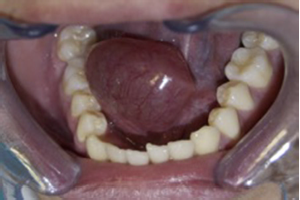

En el examen extraoral presentaba simetría facial, sin adenopatías palpables ni masa cervical evidente. Al realizar el examen intraoral se manifiesta una lesión ovoide de 7 × 4 cm en la región sublingual derecha, unilateral, que no cruza la línea media; fluctuante, de color translúcido edematoso e indoloro, que eleva y desvía la lengua al lado contralateral (fig. 1). Se realizó una hipótesis diagnóstica de ránula intraoral, la cual se complementó mediante examen imagenológico tomográfico (TC) con medio de contraste para confirmar la presencia de una lesión quística unilocular, ovalada, de baja densidad, confinada al espacio sublingual, además de evaluar su extensión anatómica confirmando su ubicación intraoral/superficial (fig. 2).